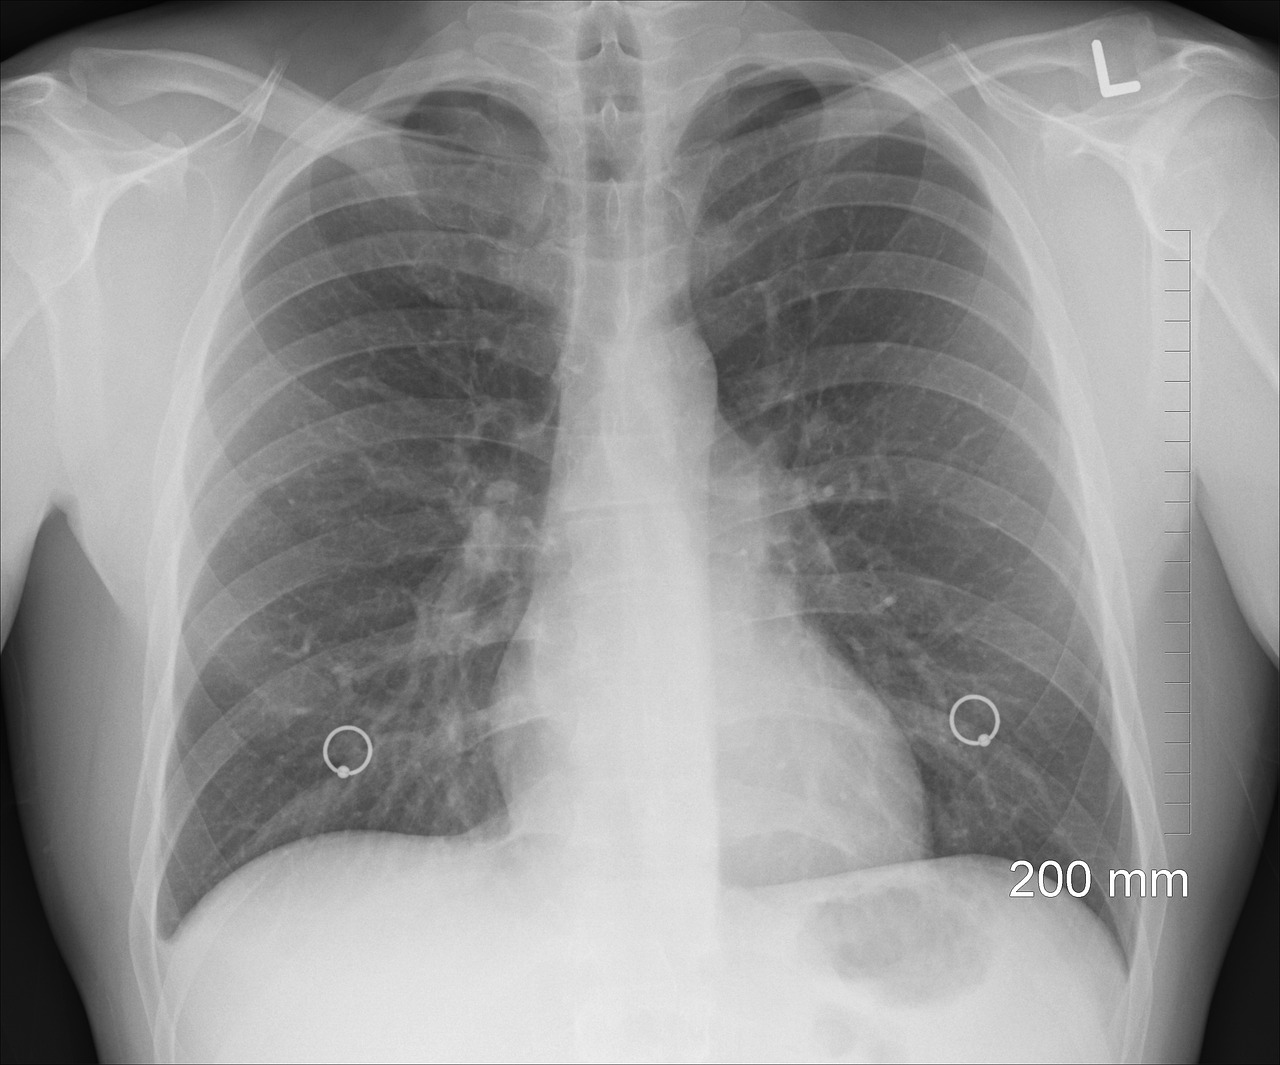

폐암과 관련한 엑스레이 사진

<폐 엑스레이 사진>